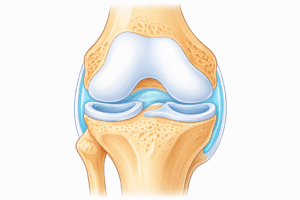

変形性膝関節症とは、膝の関節の軟骨がすり減り、炎症が起こる病気です。膝関節は、太ももの骨(大腿骨)・すねの骨(脛骨)・膝のお皿(膝蓋骨)などで構成され、骨の表面には関節軟骨というクッションがあります。この軟骨があることで、膝は滑らかに動くことができます。

しかし、加齢・負担の蓄積・筋力低下などによって軟骨がすり減ると、関節に炎症が起こります。その結果、膝の痛み・腫れ・動かしづらさなどの症状が出るようになります。

半月板損傷

半月板は膝のクッションの役割をしています。この半月板が傷つくと、関節の負担が増え、軟骨のすり減りが進むことがあります。